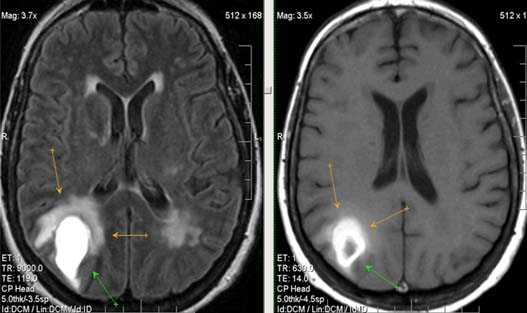

Внутримозговая гематома (граница острой и ранней подострой стадий - 3 суток), осложнившаяся внутрижелудочковым кровоизлиянием.

Внутримозговая гематома, поздний подострый период (14-21 день) с перифокальным отеком вокруг гематомы.

Внутримозговая гематома правой теменной доли. Граница поздней подострой и ранней хронической стадии. В Т2-ВИ виден ободок гемосидерина (стрелка).

Хочется подчеркнуть возможность МРТ в выявлении последствий геморрагического поражения - остается хорошо дифференцируемый по Т2 ободок гемосидерина, недоступный для визуализации при других методах нейровизуализации.

Стрелками показан ободок гемосидерина по периферии постишемической кисты.